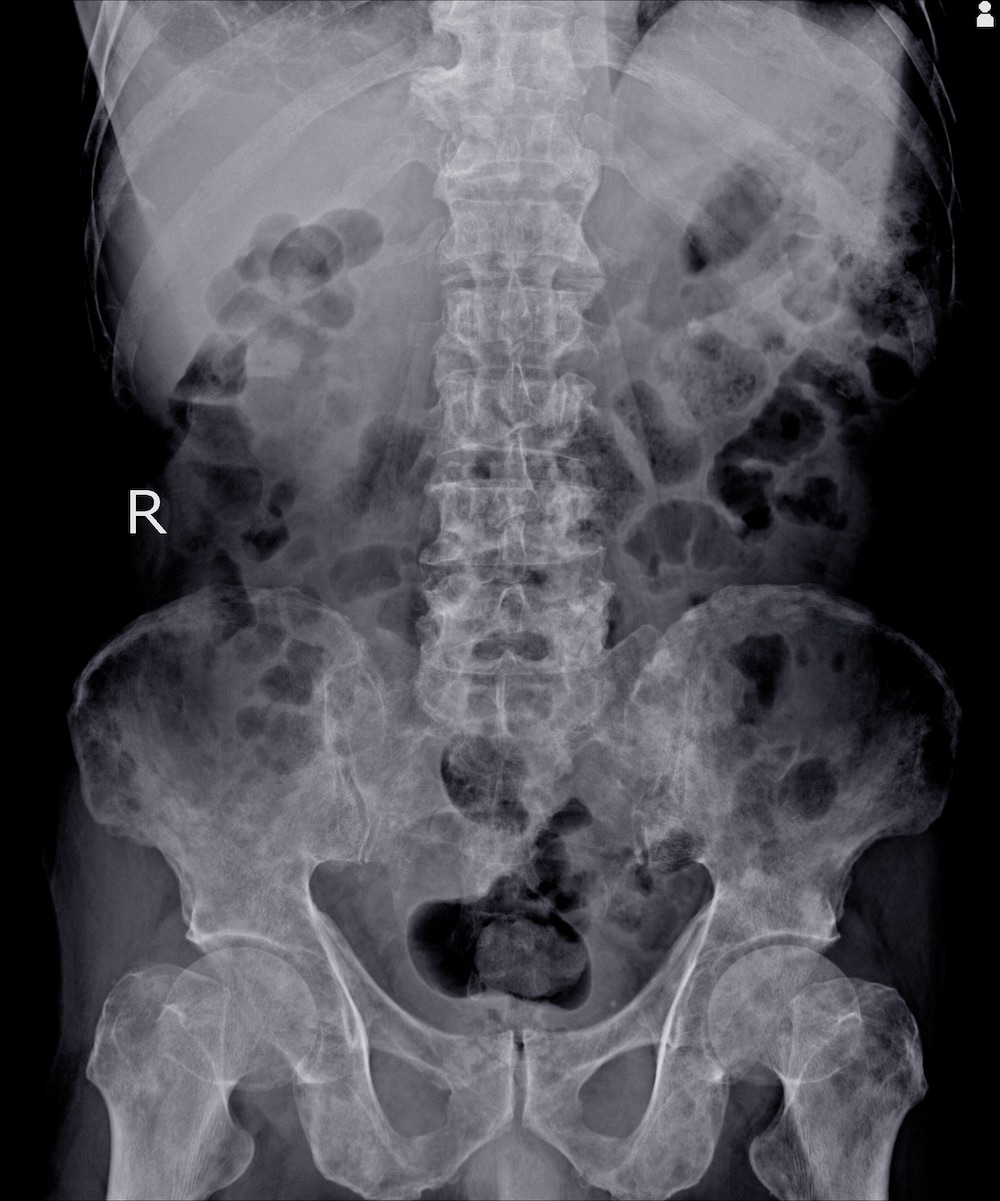

La maladie métastatique osseuse est courante chez les patients cancéreux, avec une incidence élevée en cas de myélome multiple, de cancer du sein, de la prostate, de la thyroïde, du rein et du poumon. Elle affecte considérablement la qualité de vie et la survie des patients. Bien que la douleur nociceptive causée par des médiateurs produits à partir de cellules tumorales et inflammatoires soit considérée comme une composante majeur de la douleur osseuse métastatique, il existe aussi suffisamment de preuves pour affirmer que les mécanismes neuropathiques jouent un rôle important dans la CIBP. L'objectif principal de cette étude est d'estimer la prévalence des caractéristiques de la douleur neuropathique chez les patients atteints de CIBP dans une clinique de la douleur à l'aide du questionnaire Douleur Neuropathique 4 (DN4).